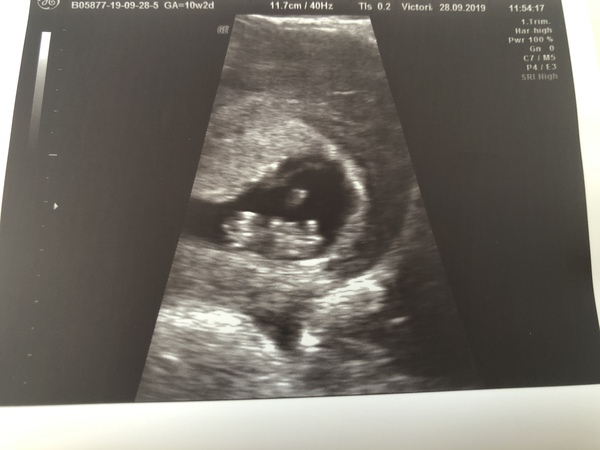

Victoria315 · 29/09/2019 14:18

I also had an early scan today. Baby measured at 8 weeks and 4 days with a due date of 6/5/19. Seeing the heartbeat was just magical 🥰